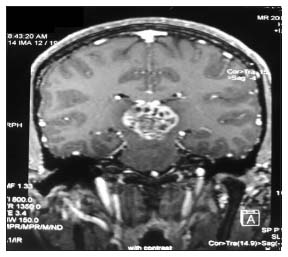

| Figure 3 Magnetic resonance imaging of hemangiopericytoma